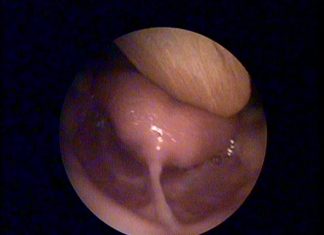

Dil Bağı Kendiliğinden Geçer mi?

Ağız boşluğu nasıl şekillenir, dil bağı kendiliğinden yırtılır mı ? dil bağı tedavisi yaşı